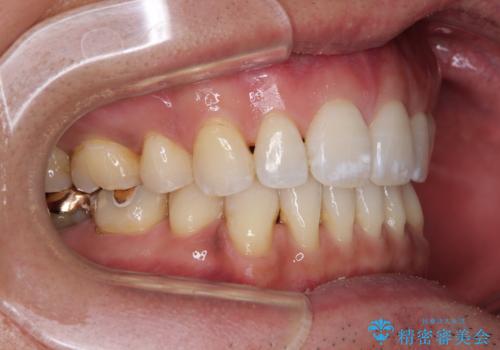

- 口元の突出感を気にして来院された患者様です。

強い咬合力と上顎前歯の傾斜により前歯が突出し、唇が閉じにくい状況であったため、上下左右の第一小臼歯4本を抜歯し、ワイヤー装置にて矯正治療を行うこととしました。

非常に咬合力が強いため、抜歯したスペースが閉じるのか不安でしたが、順調に歯が移動し、予定よりも早く治療を終えることができました。